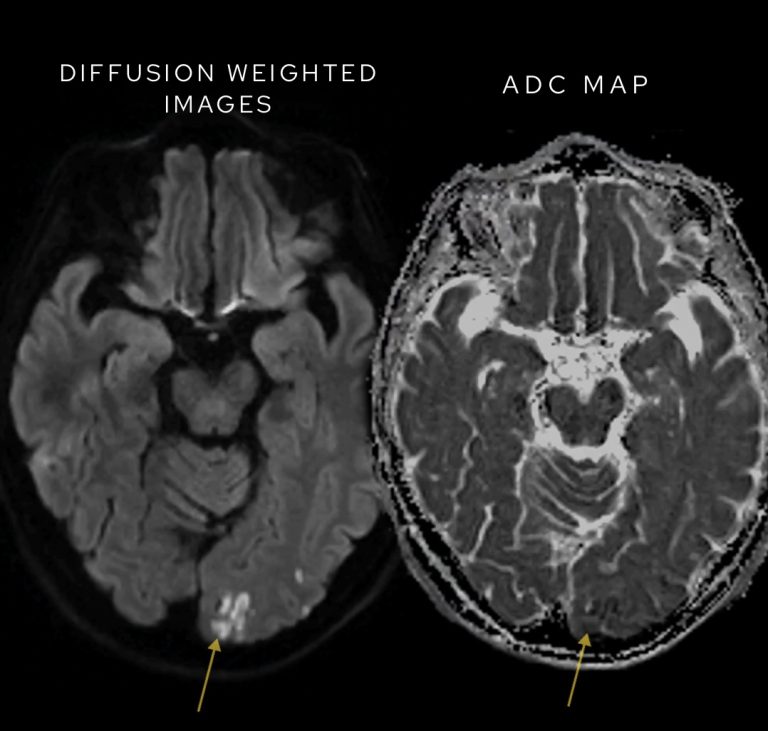

In this case we can see the centre of the lesions are low signal on DWI meaning there is ‘free diffusion’ pointing away from abscess formation.

Have a look at this separate case below where we can see restricted diffusion on DWI representing an acute stroke.

Restricted diffusion in a case of ischaemic stroke – high signal on DWI correlates with low signal on ADC.

While bright signal on DWI at higher b values may suggest restricted diffusion, it’s essential to confirm this on the ADC map:

• True restricted diffusion corresponds to areas of low ADC values (dark on the map).

• Bright spots on DWI without corresponding ADC reduction could simply reflect T2 shine-through, a phenomenon that mimics restricted diffusion but does not indicate pathology.